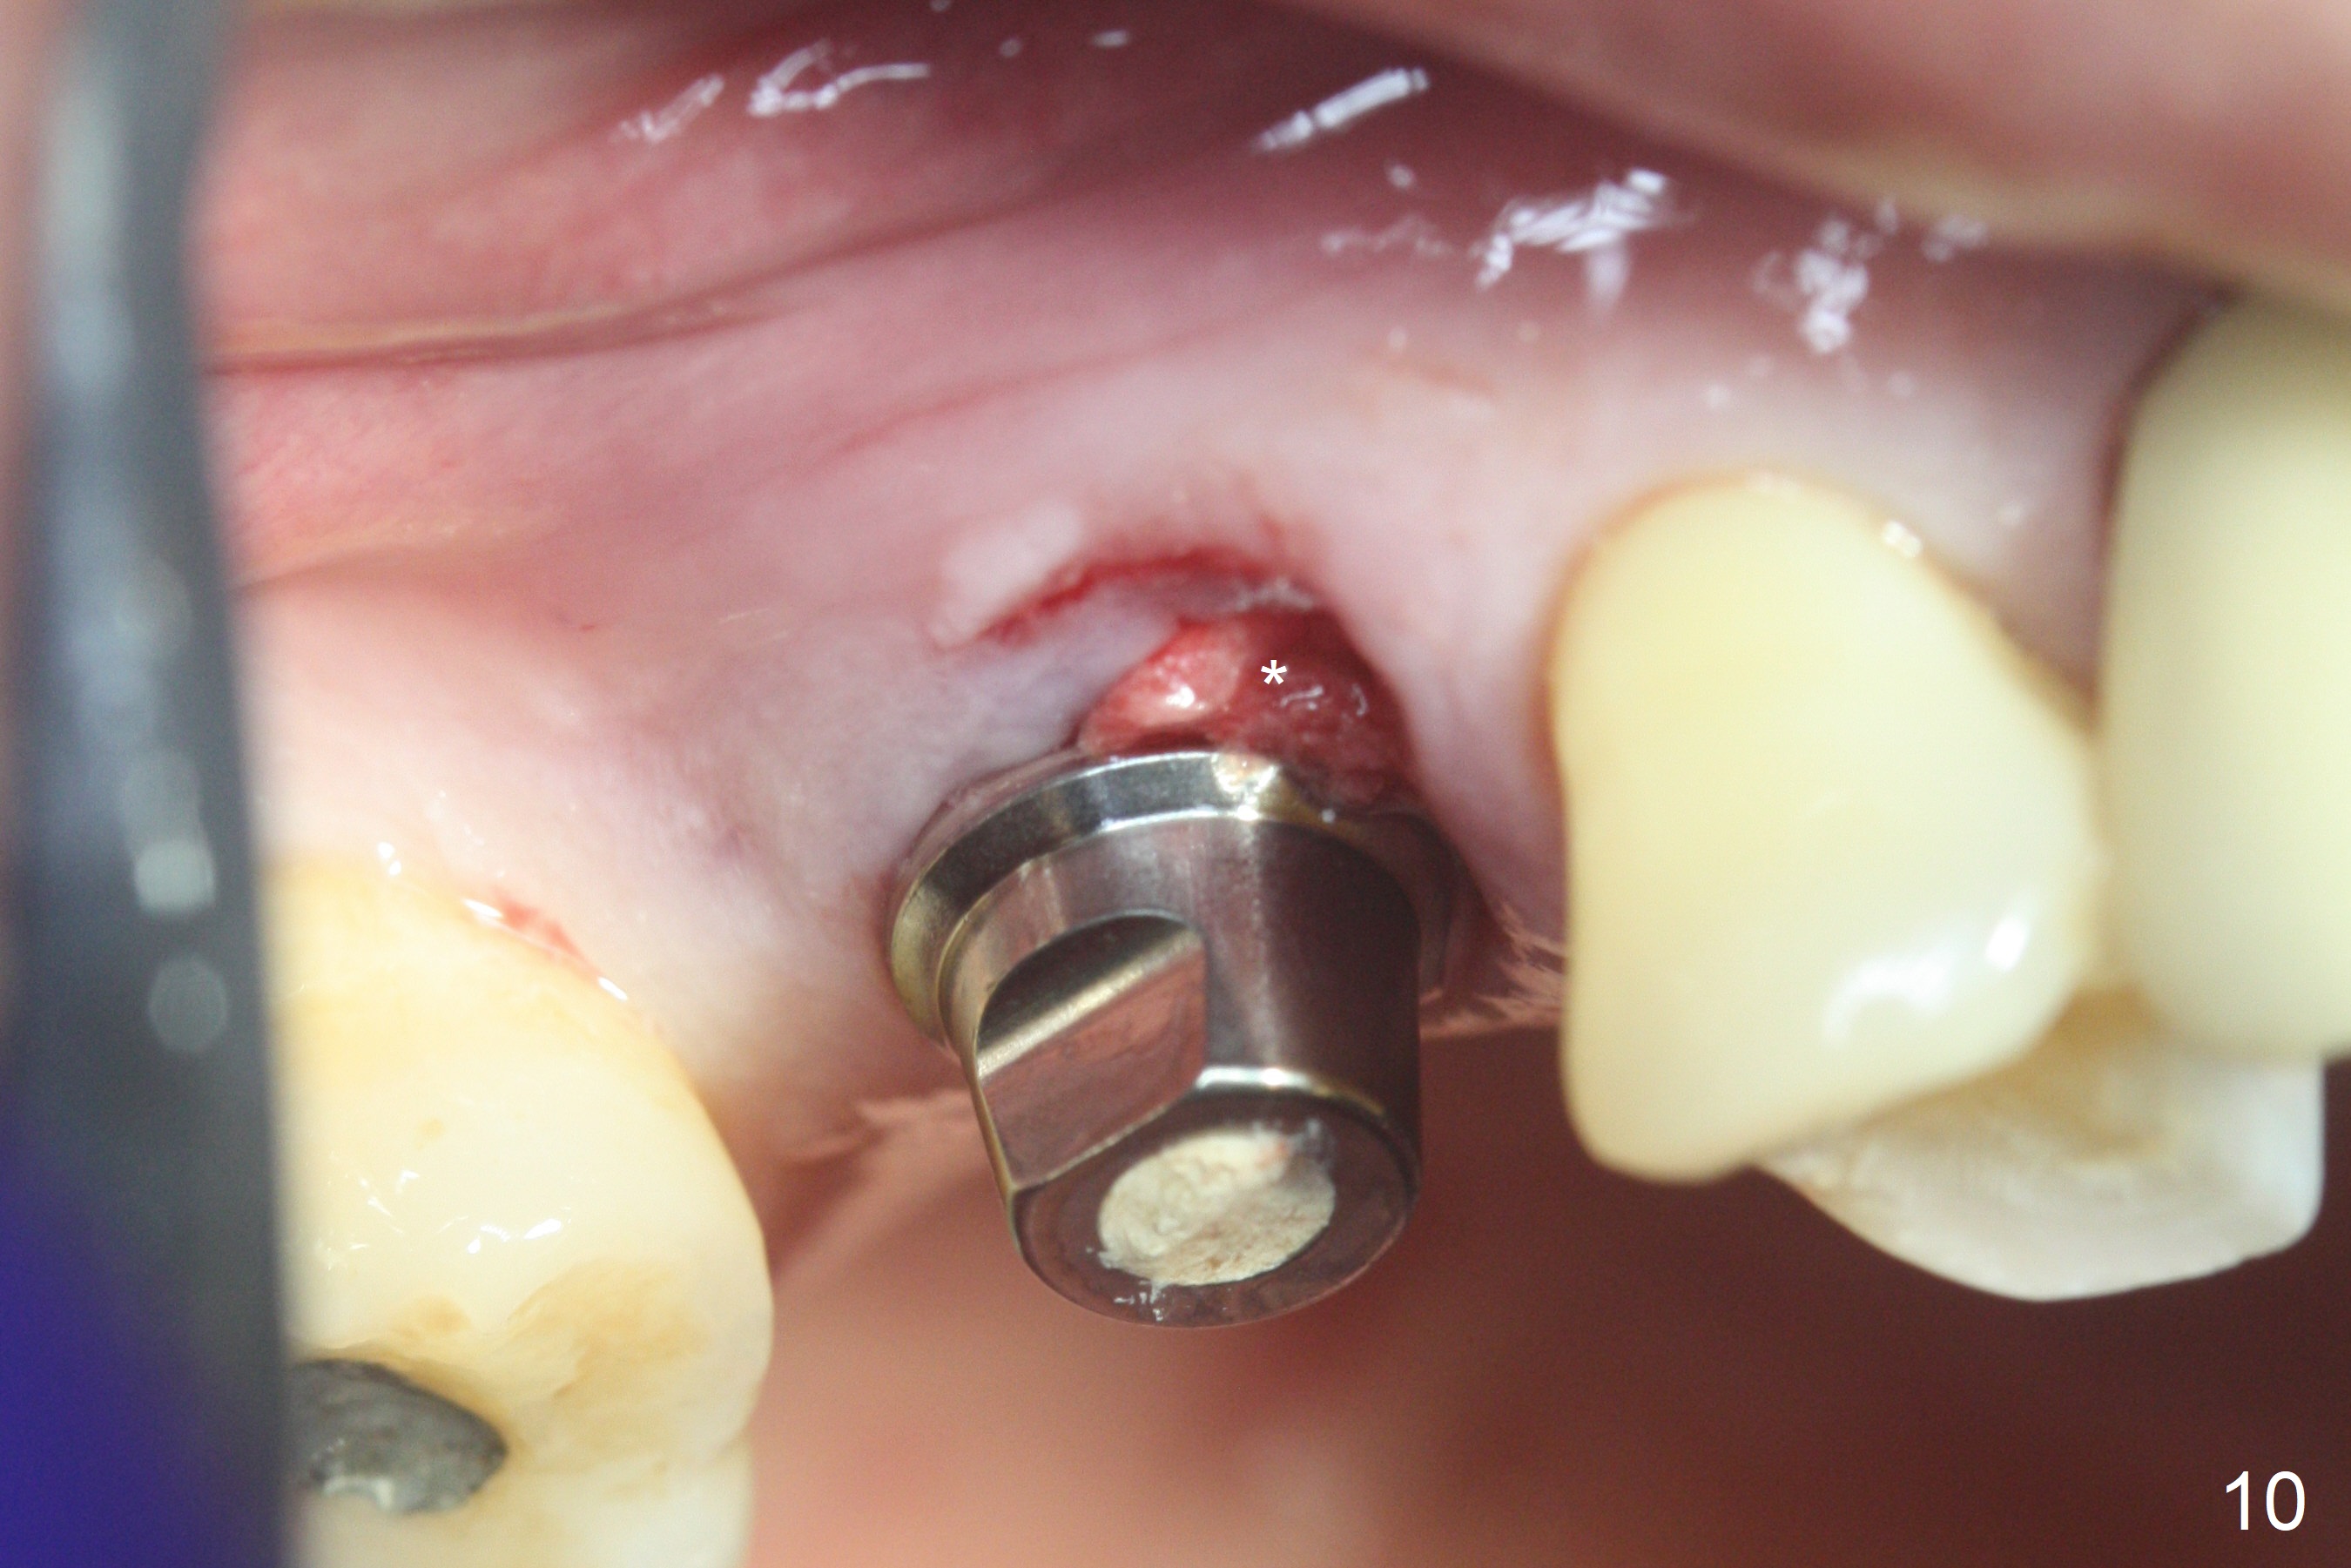

The palatal cusp of the affected 2nd premolar is apparently rotated distal (Fig.1). It is more obvious for the socket (Fig.2): the palatal (P) portion of the socket is more distal than the buccal (B) one. When the gauze is removed (Fig.3), Lindamann bur is used to remove the disto(D)palatal bone of the socket (data not shown), followed by starter drill in the DP wall obliquely (Fig.3'). Once the drill enters the bone for 1-2 mm, the bur is straightened and pushed slightly distal (Fig.3''). Fig.4 shows a parallel pin distal (overcorrect) to the original socket (Fig.4 red dashed line). Sequential osteotomy is conducted until 3.8x13 mm drill for 18 mm (Fig.5): note the 2 steps of the osteotomy (red lines). Since the apical portion of the osteotomy is larger than the drill, a larger implant than expected (5x16 mm) is placed. The implant ends up in the middle of the edentulous area (due to the stepped osteotomy; Fig.6-9; >60 Ncm). Vera allograft is placed (Fig.7-9 *) prior to and after placement of a 6.5x4(3) mm abutment (Fig.8-10). The remaining socket opening is sealed with a piece of Collagen plug (Fig.10 *). The socket is then closed by an immediate provisional (Fig.11 P). The abutment is retightened 2 months postop (Fig.12,13). The crown is cemented 4.5 months postop. Panoramic X-ray and CT are taken nearly 7 months post cementation (Fig.14,15) when the patient is ready for #30 implant guide preparation.